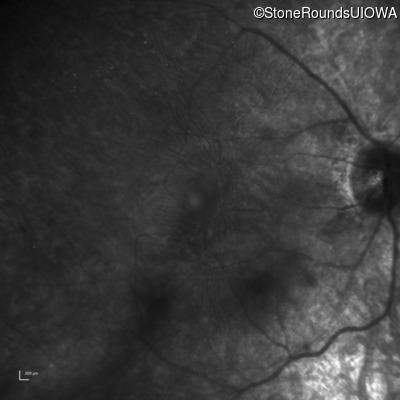

AR Retinitis Pigmentosa (IA1aiii)

Age at visit: 22 years

This 22 year old man noticed some difficulty driving at night during the past year.

Diagnosis & molecular findings

Disease Gene Allele 1 variant(s) Allele 2 variant(s) Inheritance mode

AR Retinitis Pigmentosa CLN3 Deletion Exons 9-10 Arg405Trp CGG>TGG AR